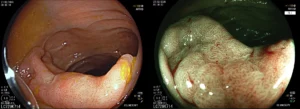

Πολύποδας παχέος εντέρου

![]()